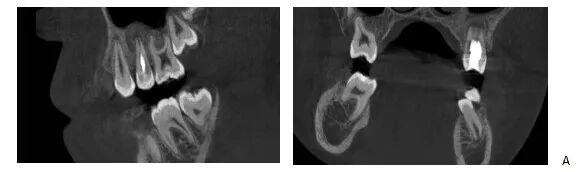

辅助检查:CBCT显示25牙根尖呈喇叭口样敞开,未发育完全,根尖低密度暗影。

CBCT矢状面显示25牙根尖未发育完成,根尖阴影

CBCT冠状面显示25牙根尖未发育完成,根尖阴影